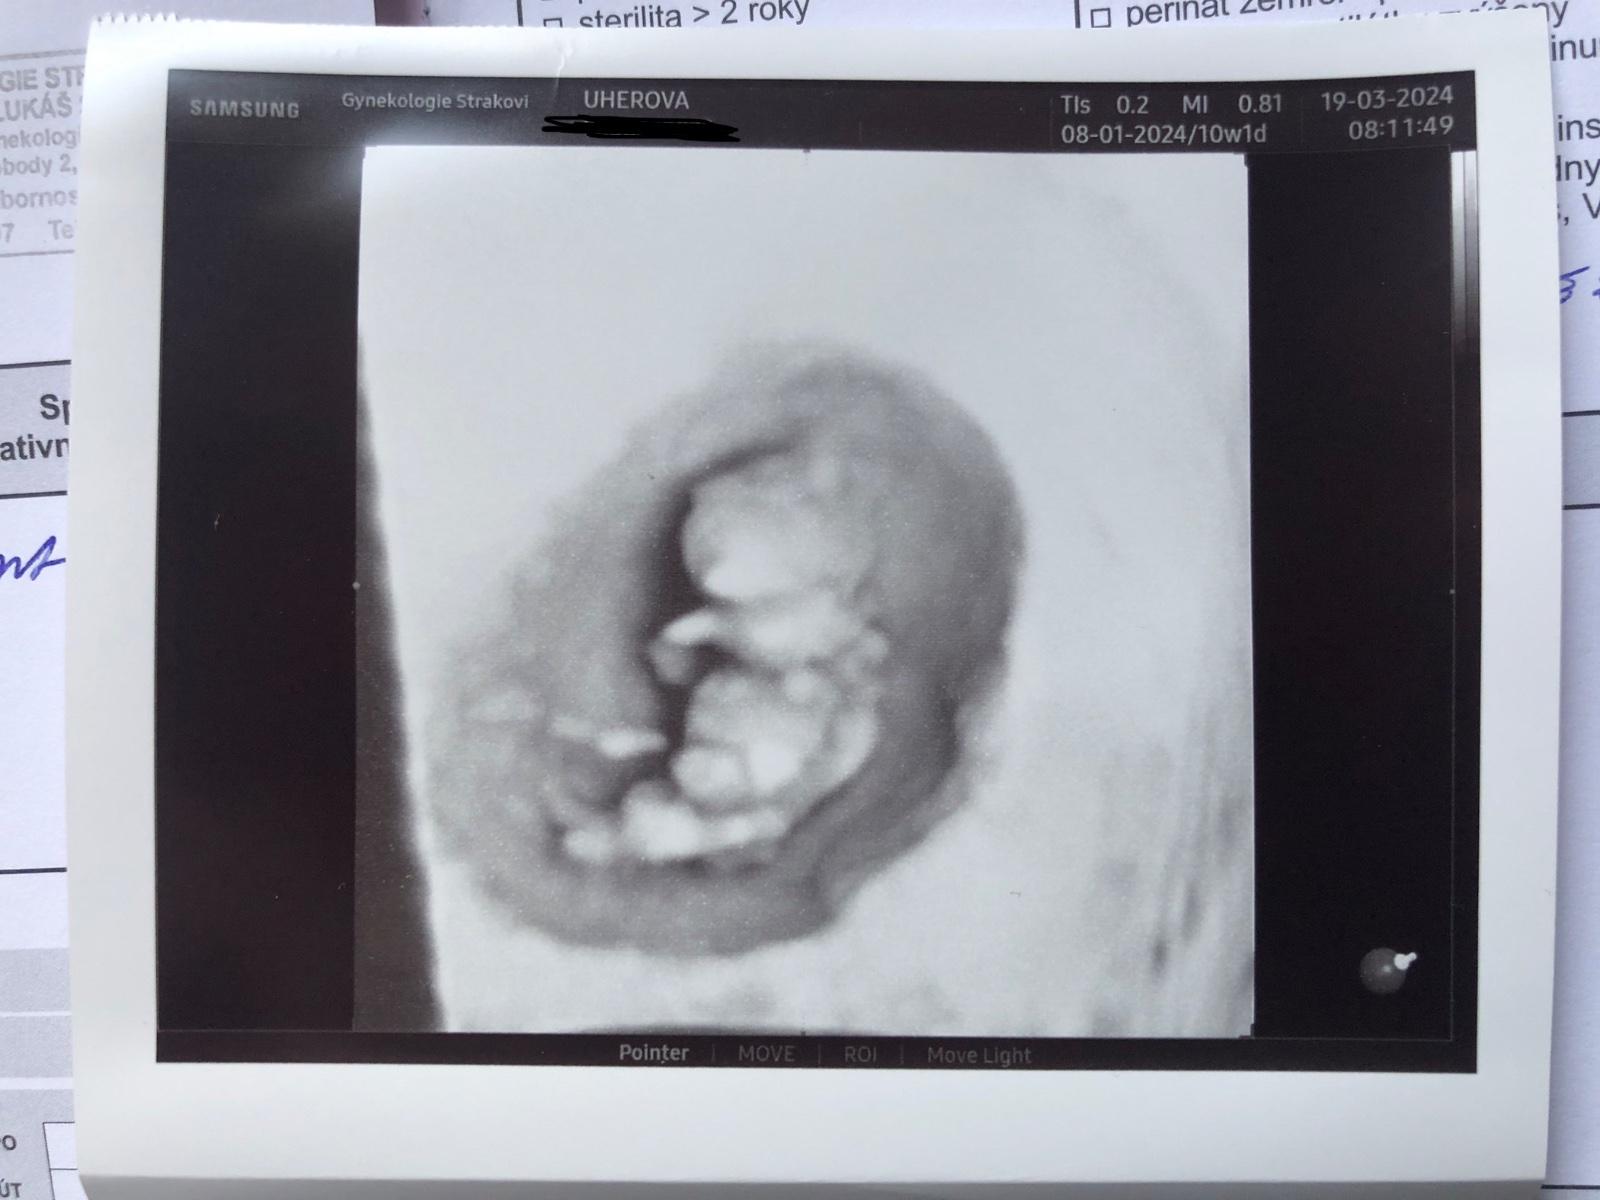

@aquenka tak holky, už mám po kontrole a to maličké pěkně roste dnes 10+1tt, malé odpovídá 10+0tt ❤️ a měří 3,2cm 🥹 na prvni screening jsem objednaná 9.4☺️